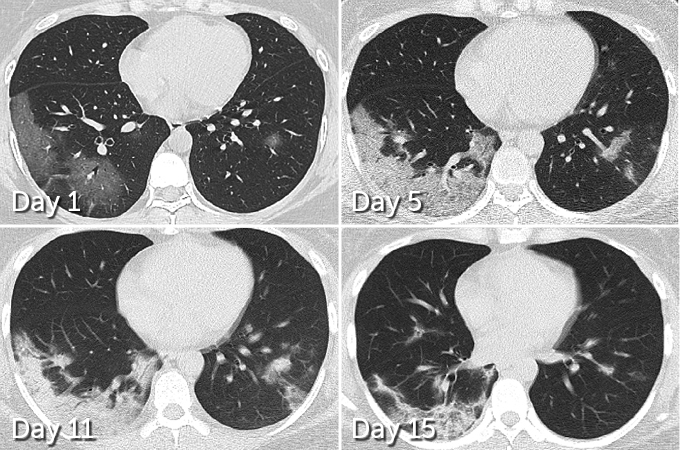

In 70 patients who survived COVID-19 pneumonia, 66 had some level of lung damage visible in CT scans taken before hospital discharge, researchers report March 19 in Radiology. The damage ranged from dense clumps of hardened tissue blocking blood vessels within the tiny air sacs called alveoli, which absorb oxygen, to tissue lesions around the alveoli, Yuhui Wang, a radiologist at Huazhong University of Science and Technology in Wuhan, China, and colleagues found.

But while initial lung images indicate that SARS and MERS typically set into just one lung, COVID-19 appears to be more likely to afflict both lungs right away. In 75 of the 90 patients admitted to Huazhong University Hospital with COVID-19 pneumonia from January 16 to February 17, damage was seen across both lungs, Wang and colleagues report. CT scans taken before hospital discharge revealed that 42 out of 70 patients displayed the type of lesions around the alveoli that are more likely to develop into scars.